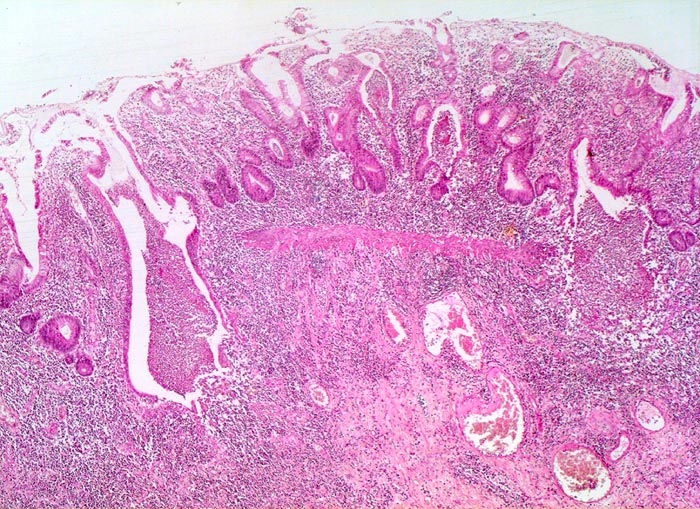

Colitis ulcerosa

Schwer gestörte Kryptenarchitektur mit zahlreichen verzweigten und unregelmässig geformten Krypten. Das Entzündungsinfiltrat in der Lamina propria ist stark verdichtet und greift auf die fibrosierte Submukosa über. Mehrere Kryptenabszesse. Die Krypten enden deutlich oberhalb der Lamina muscularis mucosae (Zeichen der Atrophie).

Kolektomie wegen chronischer therapierefraktärer Kolitis.